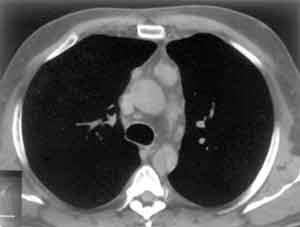

Рис. 2. Преваскулярные лимфоузлы.